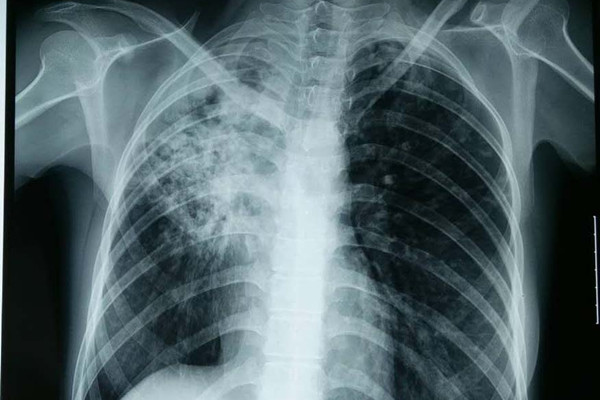

大马结核病(TBC)疫情警钟敲响!随着国内在短短时间内激增10个感染群,医学专家发出紧急呼吁,提醒民众在来临的佳节出行与回乡高峰期,务必升级个人防疫措施,严防这一“潜伏杀手”在社区大规模扩散。

值得关注的是,并非所有结核病都具备传染性。山姆加纳丹医生科普道,传播风险主要源自活动性肺结核,病菌通过空气飞沫传播;而肺外结核(如影响骨骼、淋巴或脊柱)通常不涉及呼吸道,因此不具传染性。他呼吁公众科学理性看待结核病,避免对患者产生不必要的恐慌或污名化,但必须确保确诊者完成整个疗程,严禁中途停药,以免产生更具威胁的“耐药性”结核病。